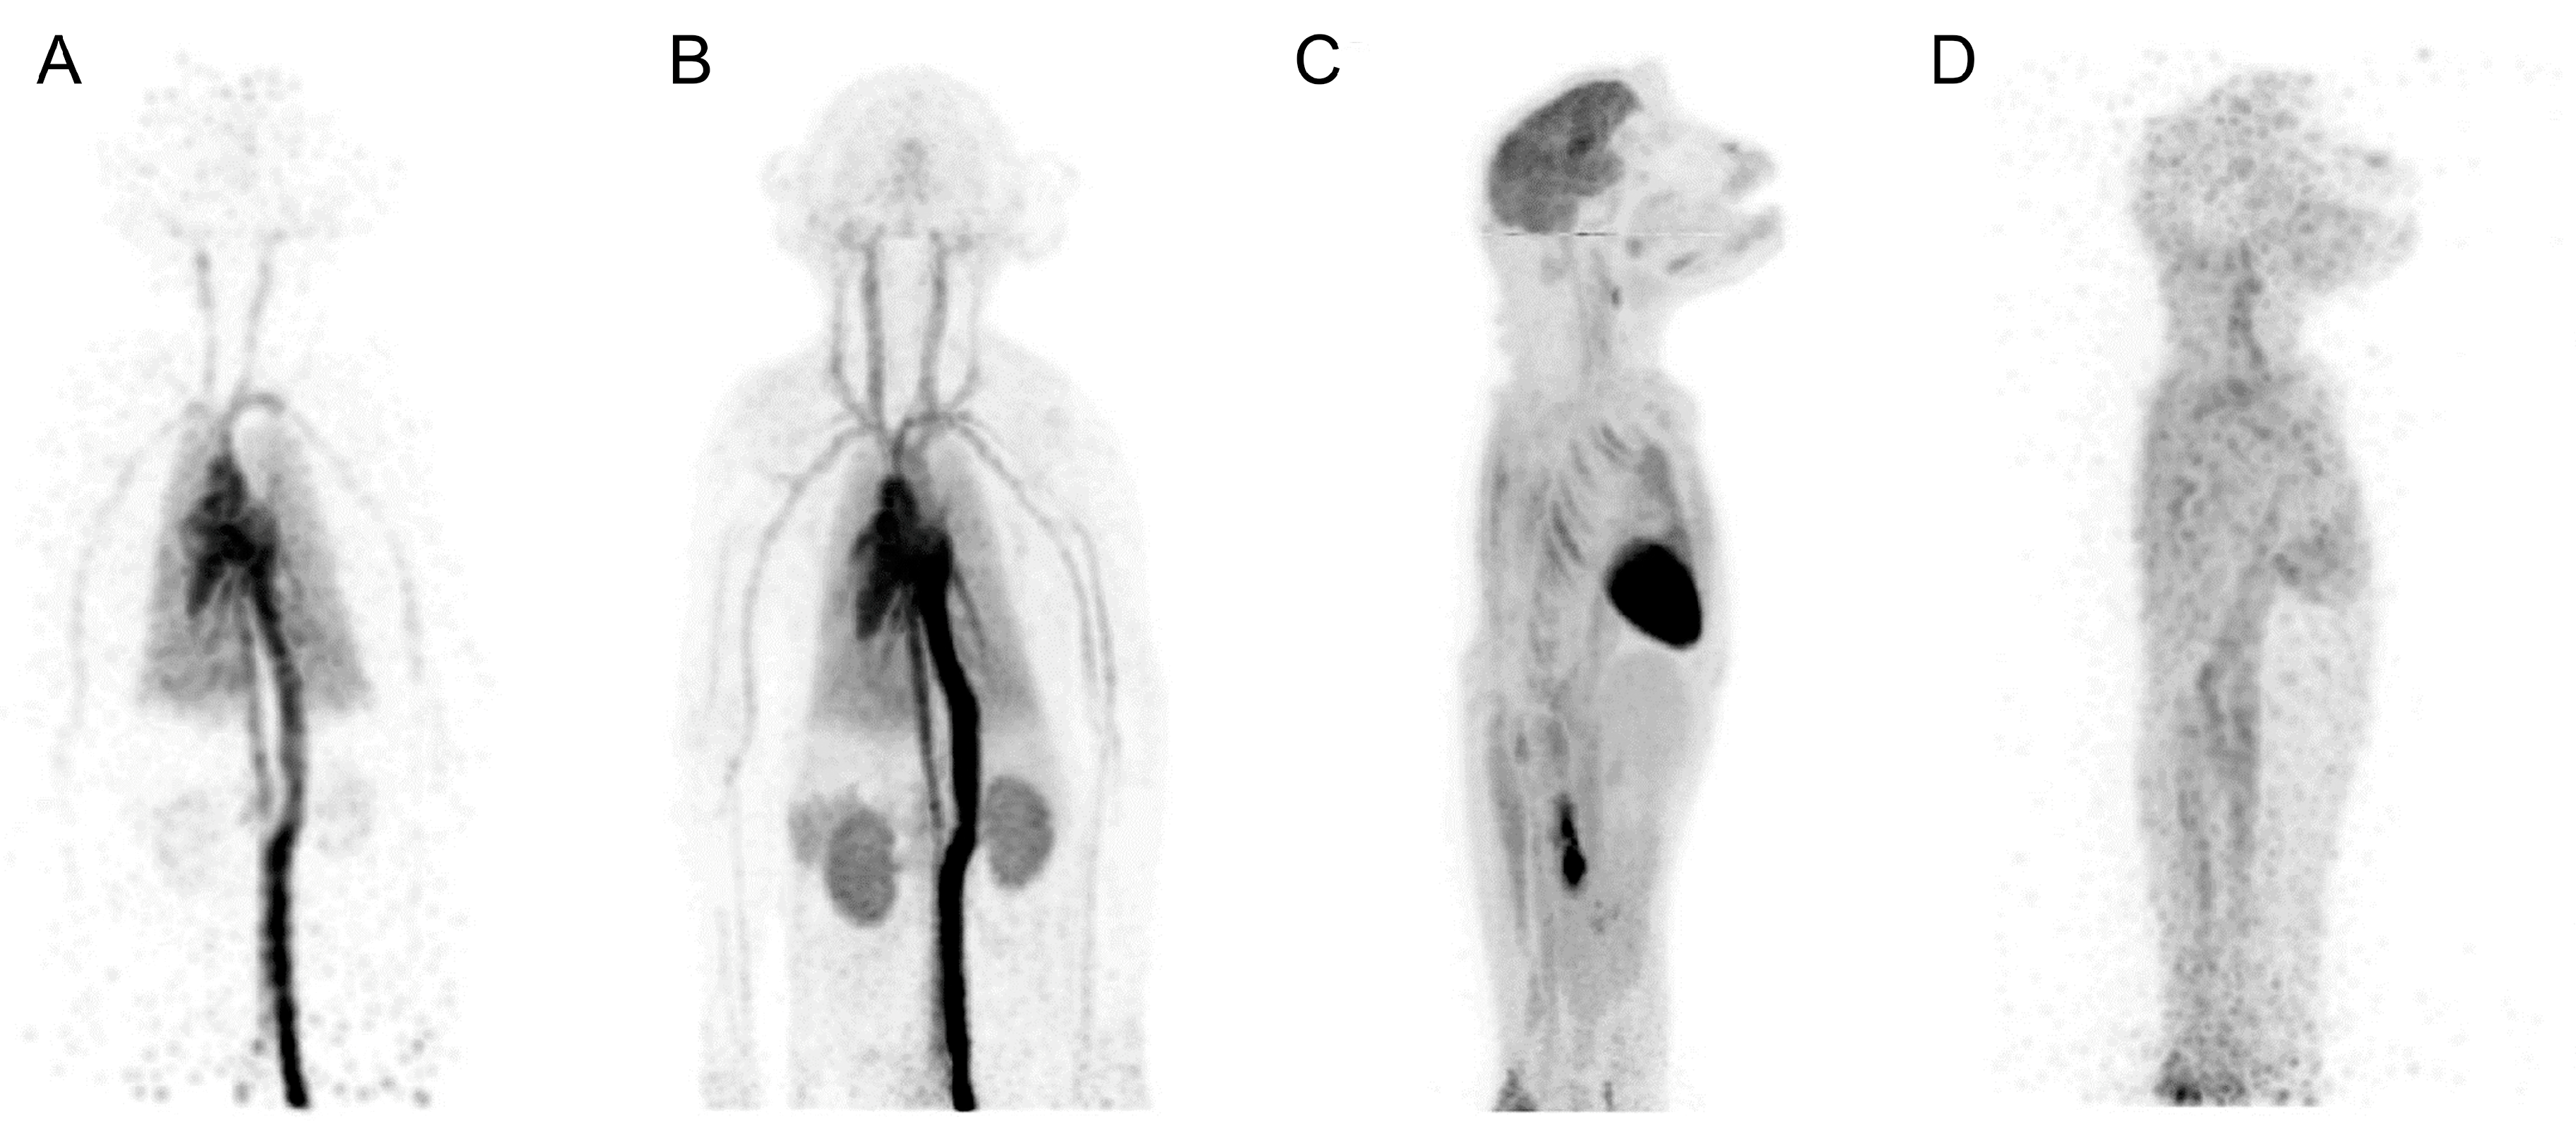

- Naninck, T.; Kahlaoui, N.; Lemaitre, J.; Maisonnasse, P.; De Mori, A.; Pascal, Q.; Contreras, V.; Marlin, R.; Relouzat, F.; Delache, B.; et al. Computed tomography and [18F]-FDG PET imaging provide additional readouts for COVID-19 pathogenesis and therapies evaluation in non-human primates. iScience 2022, 25, 104101. [Google Scholar] [CrossRef]